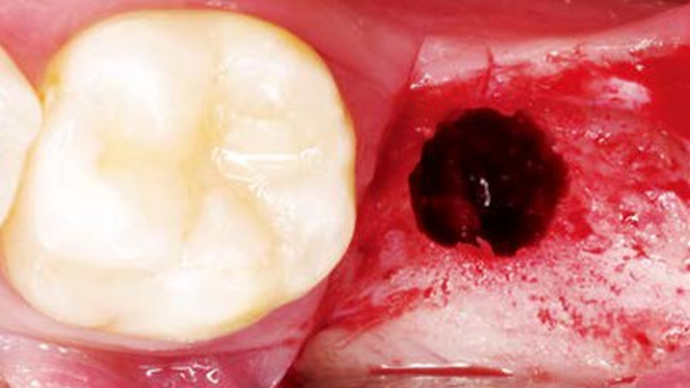

Clinical case: Single molar implant with bone augmentation

- Courtesy of Dr. Jung Sam Lee, Korea -

Keywords

AnyOne, bone augmentation, osteotomy socket, peri-implant tissue, autogenous bone, GBR, single replacement, Auto-Max, Dr. Jung Sam Lee

Products:

AnyOne implant system, Auto-Max